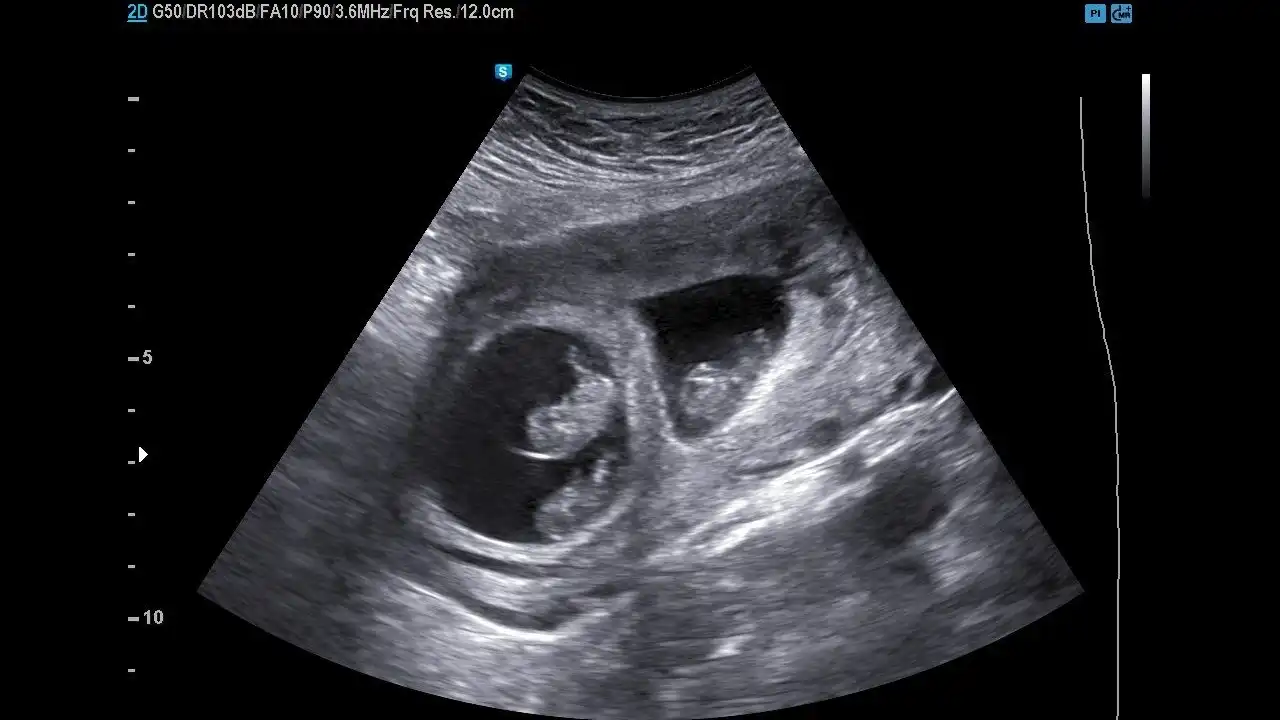

¿Qué se realiza en el ultrasonido de estos embarazos?

• ❤ Evaluación de la corionicidad, es decir si se trata de un embarazo gemelar con una placenta en la que ambos gemelos la comparten o bien dos placentas, una para cada gemelo, ya que de acuerdo a ello será la vigilancia en estos embarazos

• ❤ Si son embarazos gemelares con una sola placenta, la evaluación y el seguimiento deberá ser más estrecho, ya que que hay mayor riesgo de complicaciones en estos embarazos.

• ❤ La ecografía es el mejor método diagnóstico no sólo para identificar una gestación gemelar, sino también para catalogarla y especificar su corionicidad (número de placentas) y su amniocidad (número de bolsas).